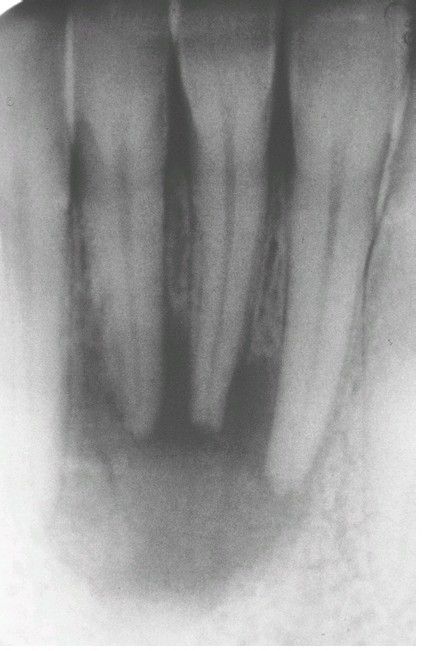

Periapical Abscess

Periapical radiolucency associated with the nonvital mandibular lateral incisor.